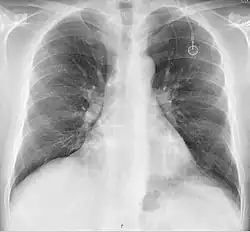

The port is then sutured on two sites to the underlying muscles. The tip of the catheter is checked for kinks and position using a fluoroscope. Besides that, aspiration of blood and contrast injection through the chemoport can also be used to confirm the position. The port is the closed in two layers (subcutaneous tissue is sutured first, followed by the skin). Sterile dressing is then placed on the port.[3] The optimum site to park the tip of the catheter is at the cavo-atrial junction or with margin of error of not more than 4 cm above the junction.[3]

A follow-up on a chest radiograph can immediately detect complications associated with the procedure such as pneumothorax, hemothorax and malpositions of the catheter. However, routine chest radiography is not needed due to the low complication rates associated with the procedure. The chest radiograph is only done if there is clinical suspicion of a complication.[4]